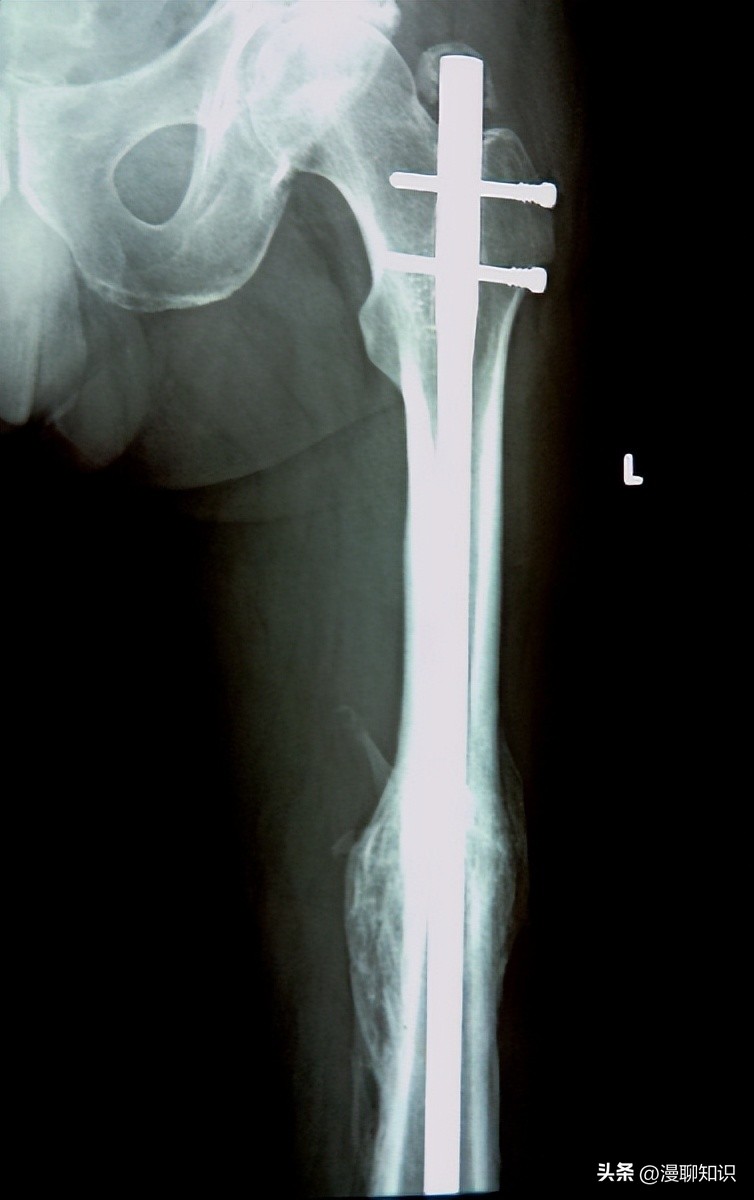

影像学检查呈亚急性或慢性骨髓炎表现,初期X线表现可能正常,之后逐步呈溶骨性和(或)成骨性改变,后期可表现为受累骨骼骨破坏伴边缘硬化。

骨膜反应的程度取决于疾病的持续时间和所涉及的解剖部位。

骨组织活检可排除慢性感染、恶性肿瘤或其他疾病,CNO通常表现为非特异性骨髓炎,早期主要有中性粒细胞、巨噬细胞等炎性细胞浸润和骨质溶解;慢性期可见反应性骨生成、骨硬化、骨纤维化和骨增生,以淋巴细胞浸润为主,同一活检标本中可见急性、亚急性、慢性炎性反应并存。